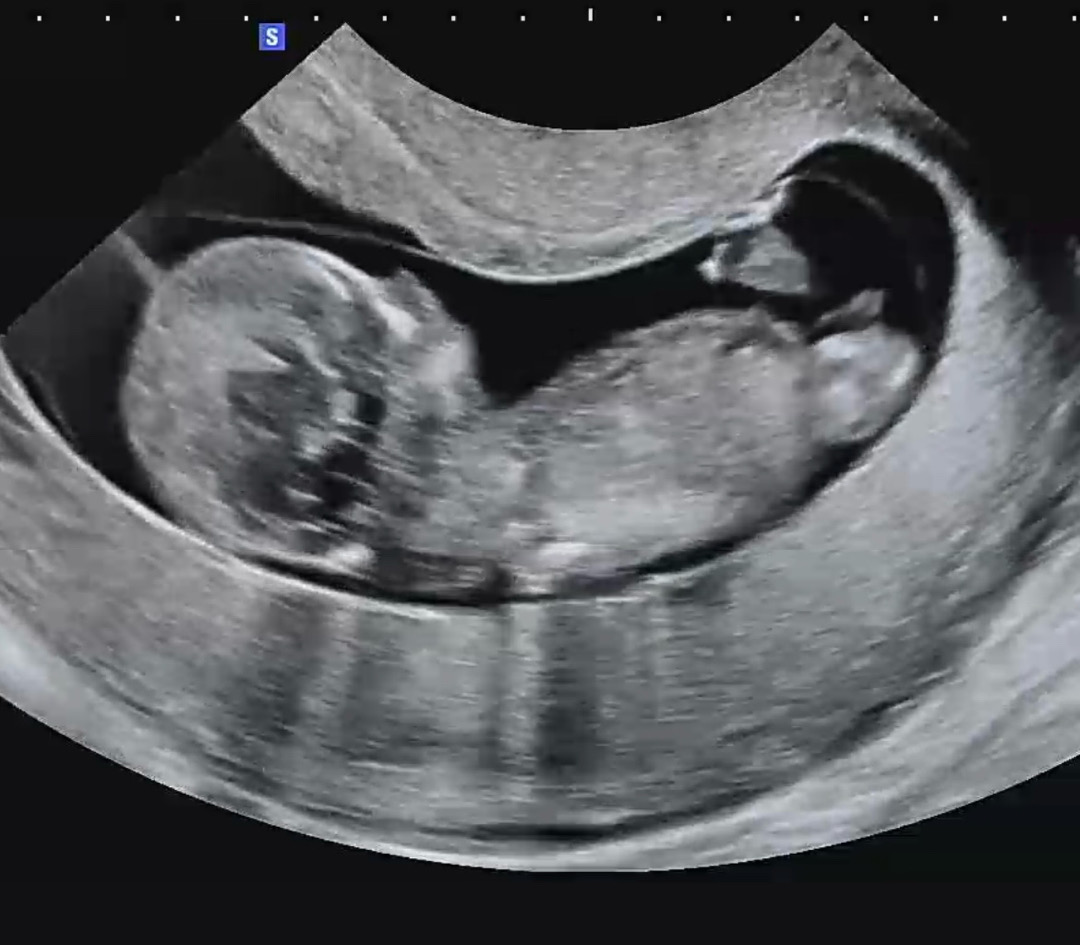

11주5일차 목투명대

9주 젤리곰에서 2주만 지났을 뿐인데 이렇게 사람형태로 보이다니 신기했어요!ㅎㅎ (아들일까요? 딸일까요?ㅎㅎ) 근데 목투명대가 2.74mm여서 13주 기형아검사 때 니프티검사 해볼까봐요 ㅜㅜ 임신초기는 늘 걱정 불안의 연속이네요..